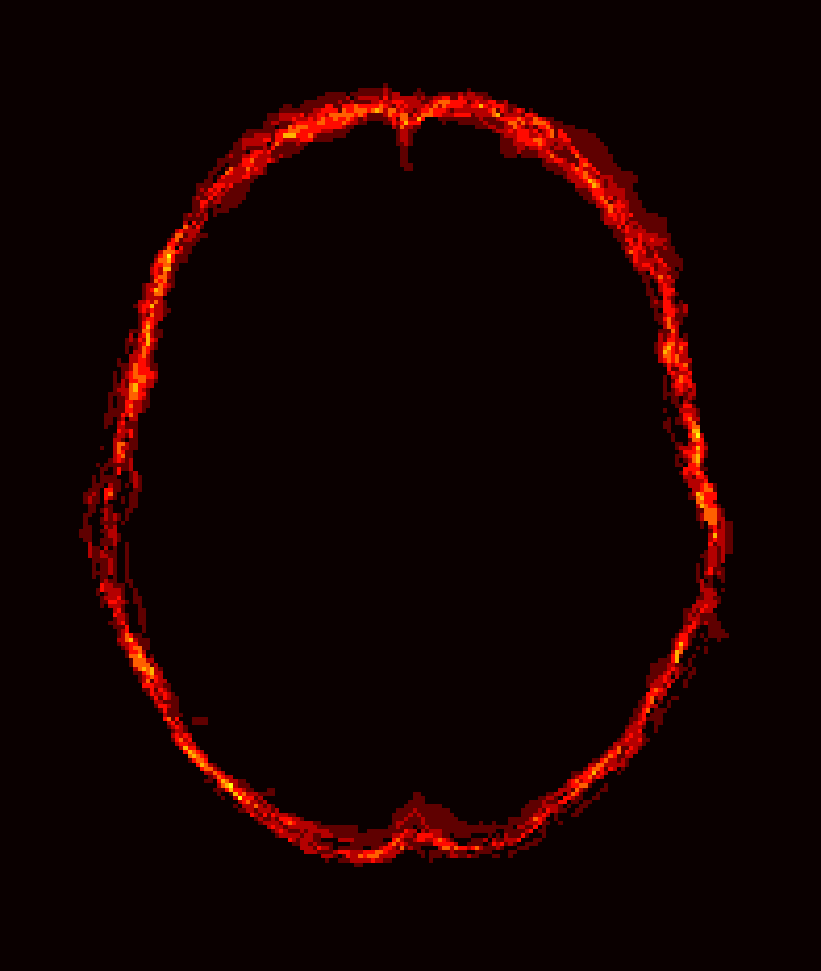

Fig. 1 shows example images from each dataset to illustrate image variability. IBSR and LPBA40 contain images from normal subjects and include large portions of the neck; BRATS has very low out-of-plane resolution; and the TBI dataset contains large pathologies and abnormal skulls.

Refer to caption

Figure 1: Illustration of image appearance variability on a selection of images from each (evaluation) database. From top to bottom: IBSR, LPBA40, BRATS and TBI.